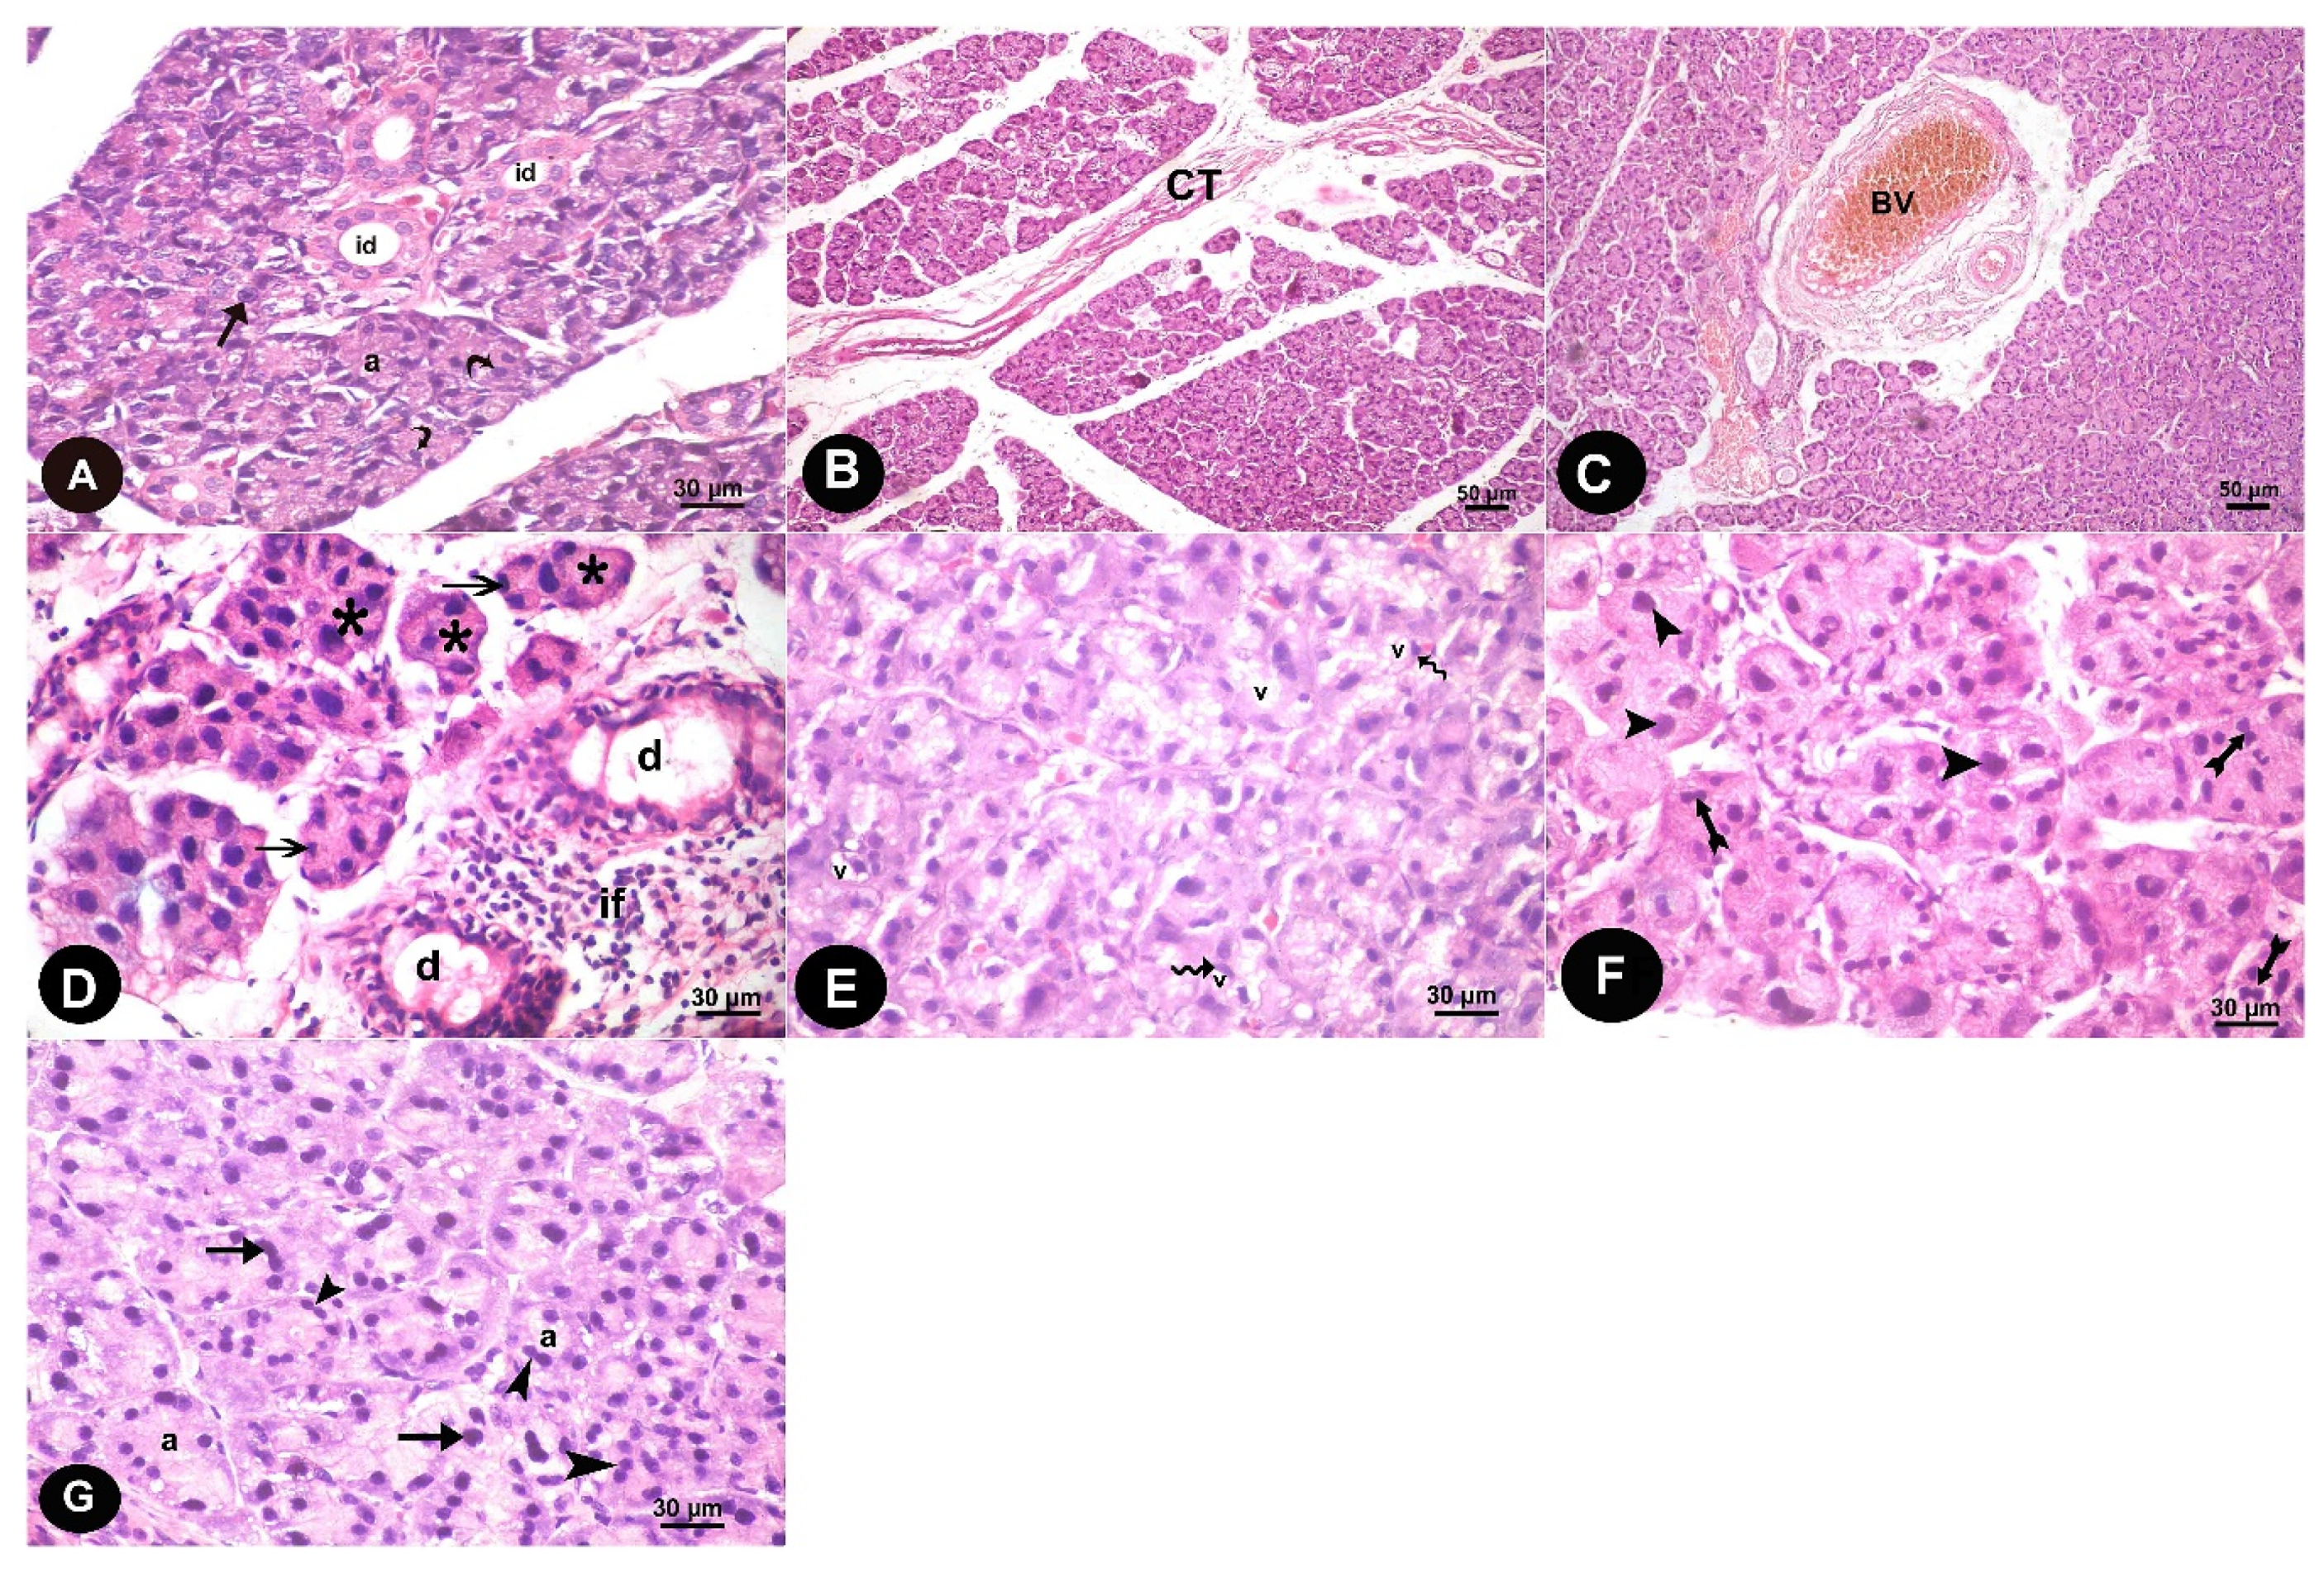

3.1.1. Light Microscope Results

3.1. Histopathological Results

3. Results